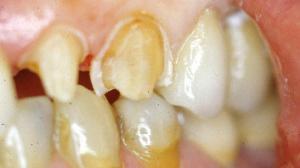

La préparation de la face vestibulaire est terminée. La limite est pour le moment supra gingivale.

II. Préparation du retour palatin

Dans le cas d'une canine, il faut englober la concavité. La fraise boule réunit en palatin les congés proximaux en traçant un sillon palatin apicalement au contact occlusal. Le bord libre sera diminué de 1 mm.

Le contact occlusal se fera sur la céramique. Un espace de 1 mm a été ménagé entre la préparation et la dent antagoniste avec la fraise boule.